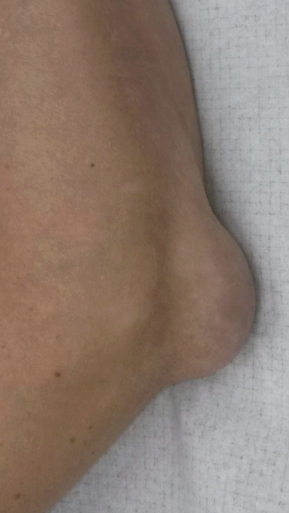

Рецидивирующий бурсит коленного сустава

Излечение за 2 процедуры ФДТ Ревиксан